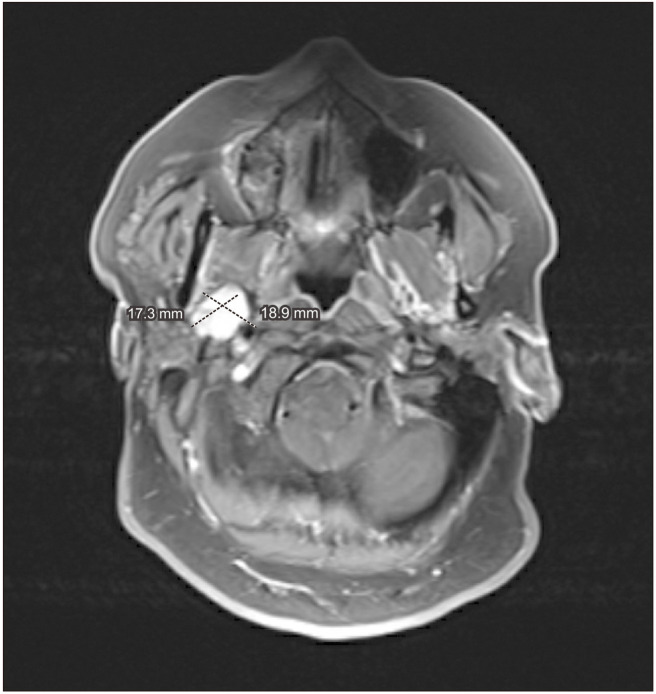

There are very few case reports of the diagnosis and management of concurrent oral cavity and parapharyngeal space tumors. We present a case involving a 49-year-old female who presented with oral cavity squamous cell carcinoma confirmed by biopsy. Initial diagnostic workup revealed a concurrent parapharyngeal mass. Diagnostic studies and surgical therapy were tailored to account for both pathological entities. The patient was treated with a combination of surgery and adjuvant therapy. The surgical strategy was designed to address both lesions simultaneously. One year post-surgery, the patient had good response to therapy with no evidence of persistent or recurrent disease. This report discusses the outcome and treatment of a rare case of concurrent squamous cell carcinoma with a complicating parapharyngeal space tumor. It explores the diagnostic process, comprehensive workup, and the surgical management.